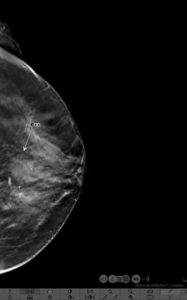

39yr old lady with history of lump in the left breast UIQ, No previous imaging done. No positive family history for CA Breast/Ovary. Pre-Menopausal Status.

Mammography- Fairly well circumscribed predominantly sold lesion in the left breast UIQ with partially obscured margins. No spiculations. No associated microcalcifications noted. Sonography: Well defined hypoechoiec lesion with smooth margins.

Low-grade Mucinous Carcinoma ER?PR- +ve HER-2 NEU -VE